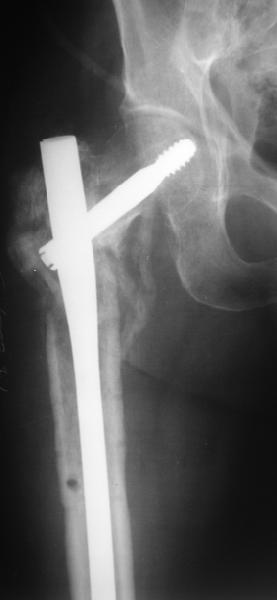

В приложении пример пациента, близкого по картине к тому, что

представил Виктор (варус и смещение периферического отломка на

поперечник кзади). Сделали как раз то, что Виктор исходно намеревался

- аппаратная коррекция и затем гамма.